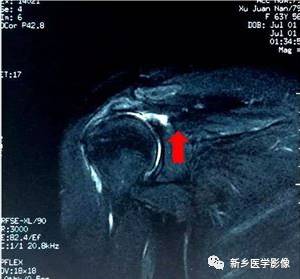

病例一:

红色箭头:冈上肌腱滑囊层撕裂